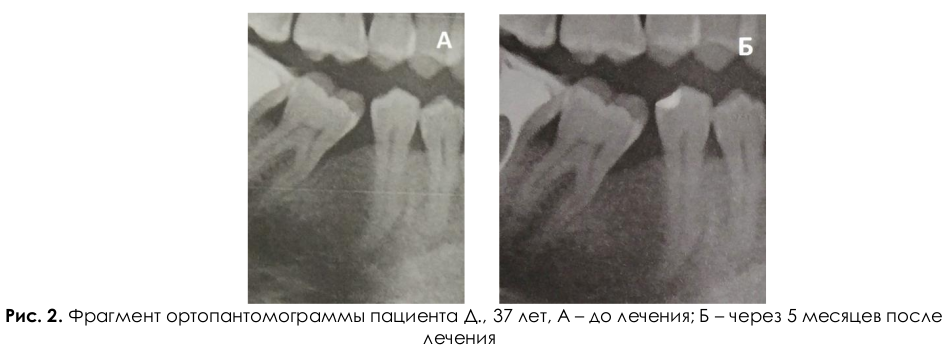

Пародонтологическая помощь в вооружённых силах российской федерации и перспективы её совершенствования - библиотека стоматологического колледжа №1